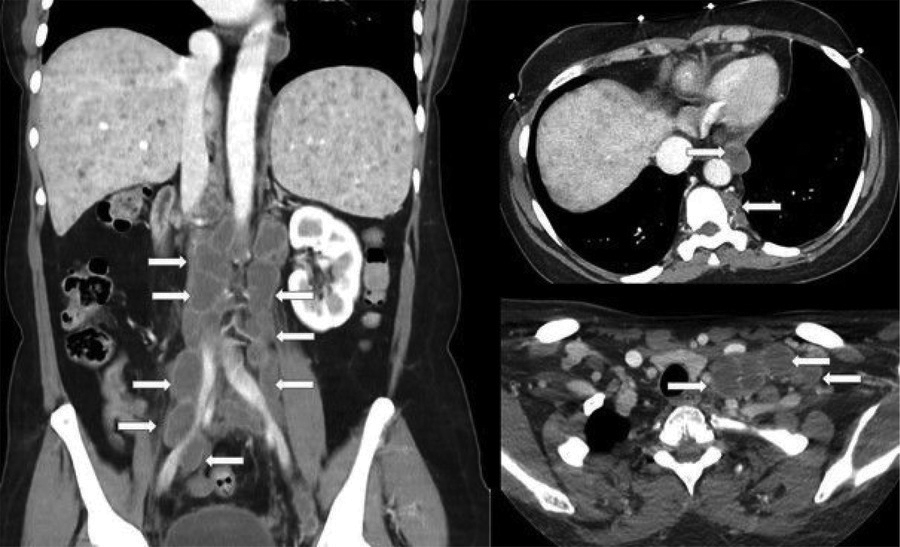

Figure 2

Coronal and axial contrast-enhanced CT